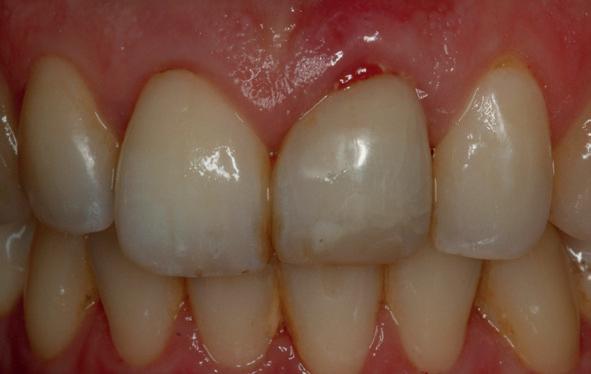

Mevrouw werd naar het Dental Design Center verwezen om een complex probleem aan het bovenfront te beoordelen en indien mogelijk te behandelen. Tien jaar geleden zijn er om esthetische redenen op de 12, 11, 21 en 22 kronen geplaatst. Helaas bleek achteraf een wortelkanaalbehandeling van de 22 noodzakelijk. Na een aantal jaar ontstond er weer een infectie apicaal aan de 22 en werd er een apex uitgevoerd. Helaas had deze behandeling niet het beoogde resultaat. Twee weken voordat ze bij mij op consult kwam, is het element geëxtraheerd en is er een partiële plaat geplaatst als tijdelijke oplossing (foto 1-3).

heeft de nadrukkelijke wens om geen brugconstructie te krijgen. Om die reden is een etsbrug of een conventionele brug geen optie. Daarom bestaat het behandelvoorstel uit vier losse kronen waarvan de 22 implantaat gedragen zal zijn. Een gedetailleerd onderzoek van de regio 22 is noodzakelijk (foto 4-6).

Uit het röntgenonderzoek blijkt dat op de locatie van de 22 veel bot verloren is gegaan en dat er niet direct een implantaat geplaatst kan worden. Om die reden is een botaugmentatie geïndiceerd. Wel zijn distaal van de 21 en mesiaal van de 23 de botpieken aanwezig die de papillen ondersteunen. Naast te weinig bot, is op de locatie 22 in bucco-linguale richting ook te weinig volume gingiva aanwezig. Daarom zal er tevens een soft tissue graft aangebracht worden. Tijdens deze behandeling wordt ook de recessie op de 23 zoveel mogelijk bedekt (foto 7 en 8).

De flap en graft worden met poly-propelene 6.0 hechtingen gefixeerd. De tijdelijke reconstructie wordt herplaatst (foto 17-20).

Na 4-6 weken kan het aangebrachte healing abutment worden vervangen door een tijdelijk abutment. Deze wordt aan de kunststof reconstructie verbonden om zo de gingiva ter plaatse van de 22 te vormen. Zo lijkt het of er geen implantaat maar nog steeds een wortel aanwezig is, wat het esthetisch eindresultaat ten goede zal komen (foto 21-23). Vanaf 4-6 maanden ziet het weefsel er gezond uit. Nu kan met de uiteindelijke restauratiefase worden gestart (foto 24 en 25).